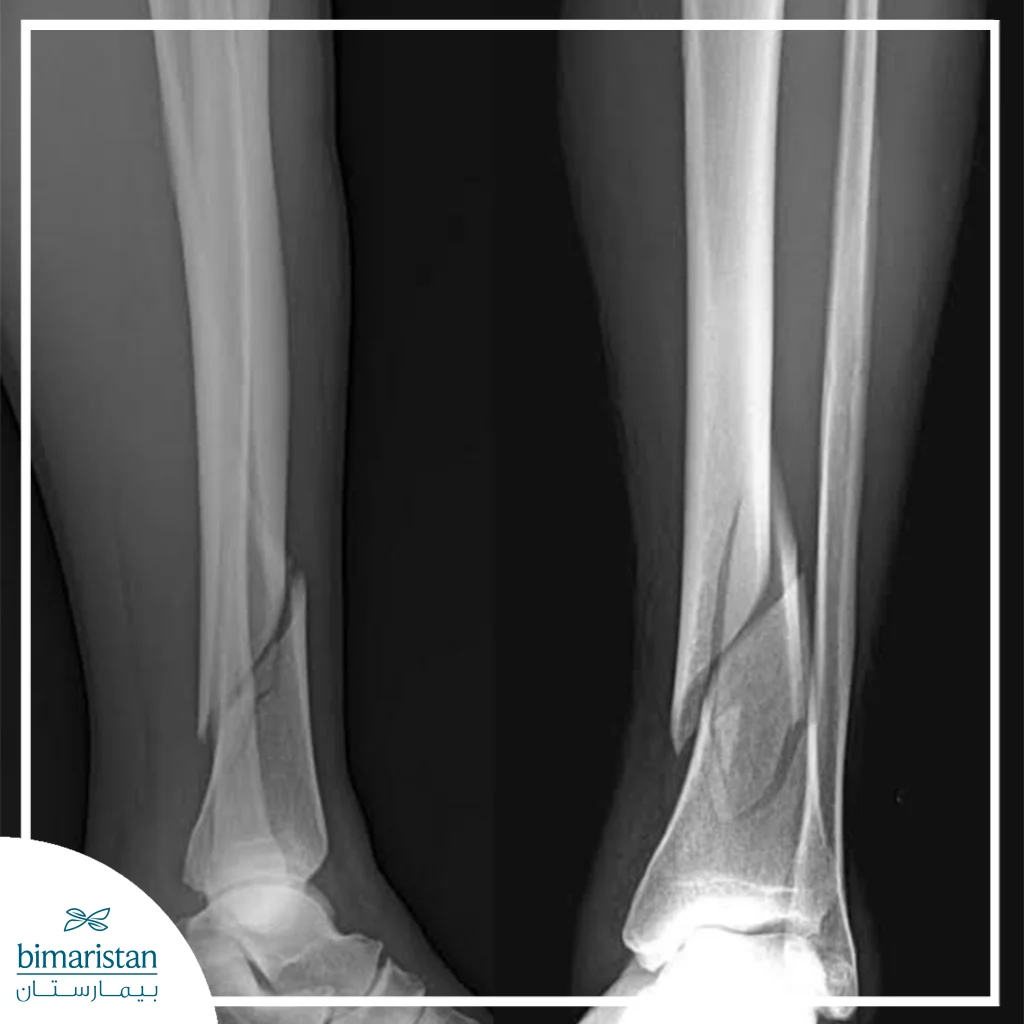

X-rays

X-rays are the primary method for determining the location and nature of a fracture, providing two-dimensional images of the bone that help doctors assess the degree of displacement of bone fragments, the presence of an open or closed fracture, and the extent to which the nearby joint has been affected. X-rays are used before and after treatment to monitor healing and ensure bone stabilization during conservative treatment or after surgery.